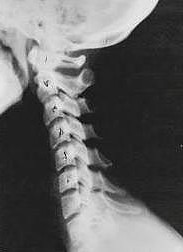

Phase One Subluxation Degeneration

Phase One Subluxation Degeneration is seen in subluxations that have been present for up to twenty years.  This phase is characterized with a loss or change in the normal curve in the spine.  On this example you can see that the normal forward (lordotic) curve is lost.  This spine even has developed a reverse curve in the neck.  The disc spaces have also begun to exhibit a slight change in shape.  One good point is that the bodies of each of the vertebrae (the square part in front) still exhibits clean clear borders.  Segmental motion  may be abnormal but overall motion is probably not affected.  Chiropractic reconstructive care for a phase one can take from 6 to 18 months.  More than 80% of people with Phase One Subluxation Degeneration have no pain.  Therefore, if left uncorrected, phase one continues to progress with time until it eventually reaches the next phase.